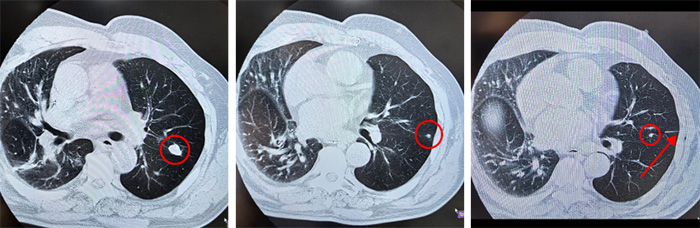

病例特点:李某,76岁,半年前发现右肺结节,行胸腔镜右肺上叶尖段切除术,病理确诊肺原发骨肉瘤,经3周期化疗后,患者拒绝继续治疗,在随诊过程中发现左肺3个结节且逐渐增大,位置集中在左肺上叶尖后段的c亚段和部分上舌段,患者手术意愿强烈。

手术特点:目标结节(红色圆圈3个)位于左肺上叶,需切除左肺上叶部分尖后段和部分上舌段,经科室讨论后,采用了“结节部位双认证”的模式,即术前CT引导穿刺定位最低结节(红色剪头所指为穿刺针,即第一认证),便于术中明确拟切除的结节在预定手术切除肺段范围内

术中游离切断供应“目标肺段”的动脉分支,静脉注射吲哚菁绿,将胸腔镜开启荧光模式,显示出“目标肺段”和“健康肺段”的分界(图2染色的为健康肺段,即第二认证),并确保目标结节在“目标肺段”内,将目标肺段予以切除。